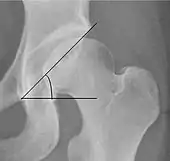

Center-edge angle of Wiberg

The superior-lateral coverage of the femoral head.

• >20° (<55 years old)[notes 2]

• <24° (>55 years old)[notes 2]

• >40° indicates overcoverage